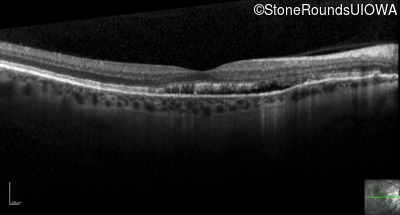

Optical Coherence Tomography - Left - 20/30 -2 sc

Exemplar / OCT Stack

OCT Stack